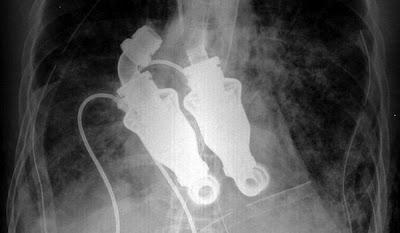

El checo Jakub Halik es el primer hombre del mundo que sobrevive desde hace ya seis meses sin corazón, después de que el suyo fuera extirpado para ser sustituido por dos bombas.

El paciente, un bombero de 37 años, tenía un tumor maligno en el corazón, y la única alternativa que se le ofrecía en lugar de un trasplante inmediato era la implantación de las bombas, una que manda la sangre por la aorta, y la otra a los pulmones. Un órgano completo sustituido por un dispositivo, ¿esto es posible? Veamos que si, lo es!.

Lo más costoso fue fijar la presión de bombeo de cada uno de los dispositivos, pues la sangre que va a los pulmones debe tener menor presión para que éstos no se irriten. El único inconveniente es cargar con las pilas bajo los brazos. Los acumuladores no se ven, no pesan mucho y duran entre 8 y 12 horas, mientras que el equipo regulador se lleva como una riñonera. En el caso de Halik, las revoluciones están fijadas para una actividad normal, no para correr, hacer deporte ni subir por una escalera. “No es capaz de reaccionar al esfuerzo”, aseveró Pirk.

Hay que aclarar que Halik ha sido el segundo en la historia que ha recibido un corazón artificial sin pulso, es decir, no tiene válvulas. "La experiencia confirma que la vida útil de las bombas es de 5 o 10 años. Pero desde un punto de vista biológico, es difícil responder a la pregunta", dijo la doctora checa Netuka a través del sitio web Medical Tribune. Solo el tiempo dirá que tan bueno es este tan útil soporte de vida, hasta ahora a demostrado se eficaz, dando el tiempo necesario hasta que a Halik le puedan transplantar un corazón biológico.